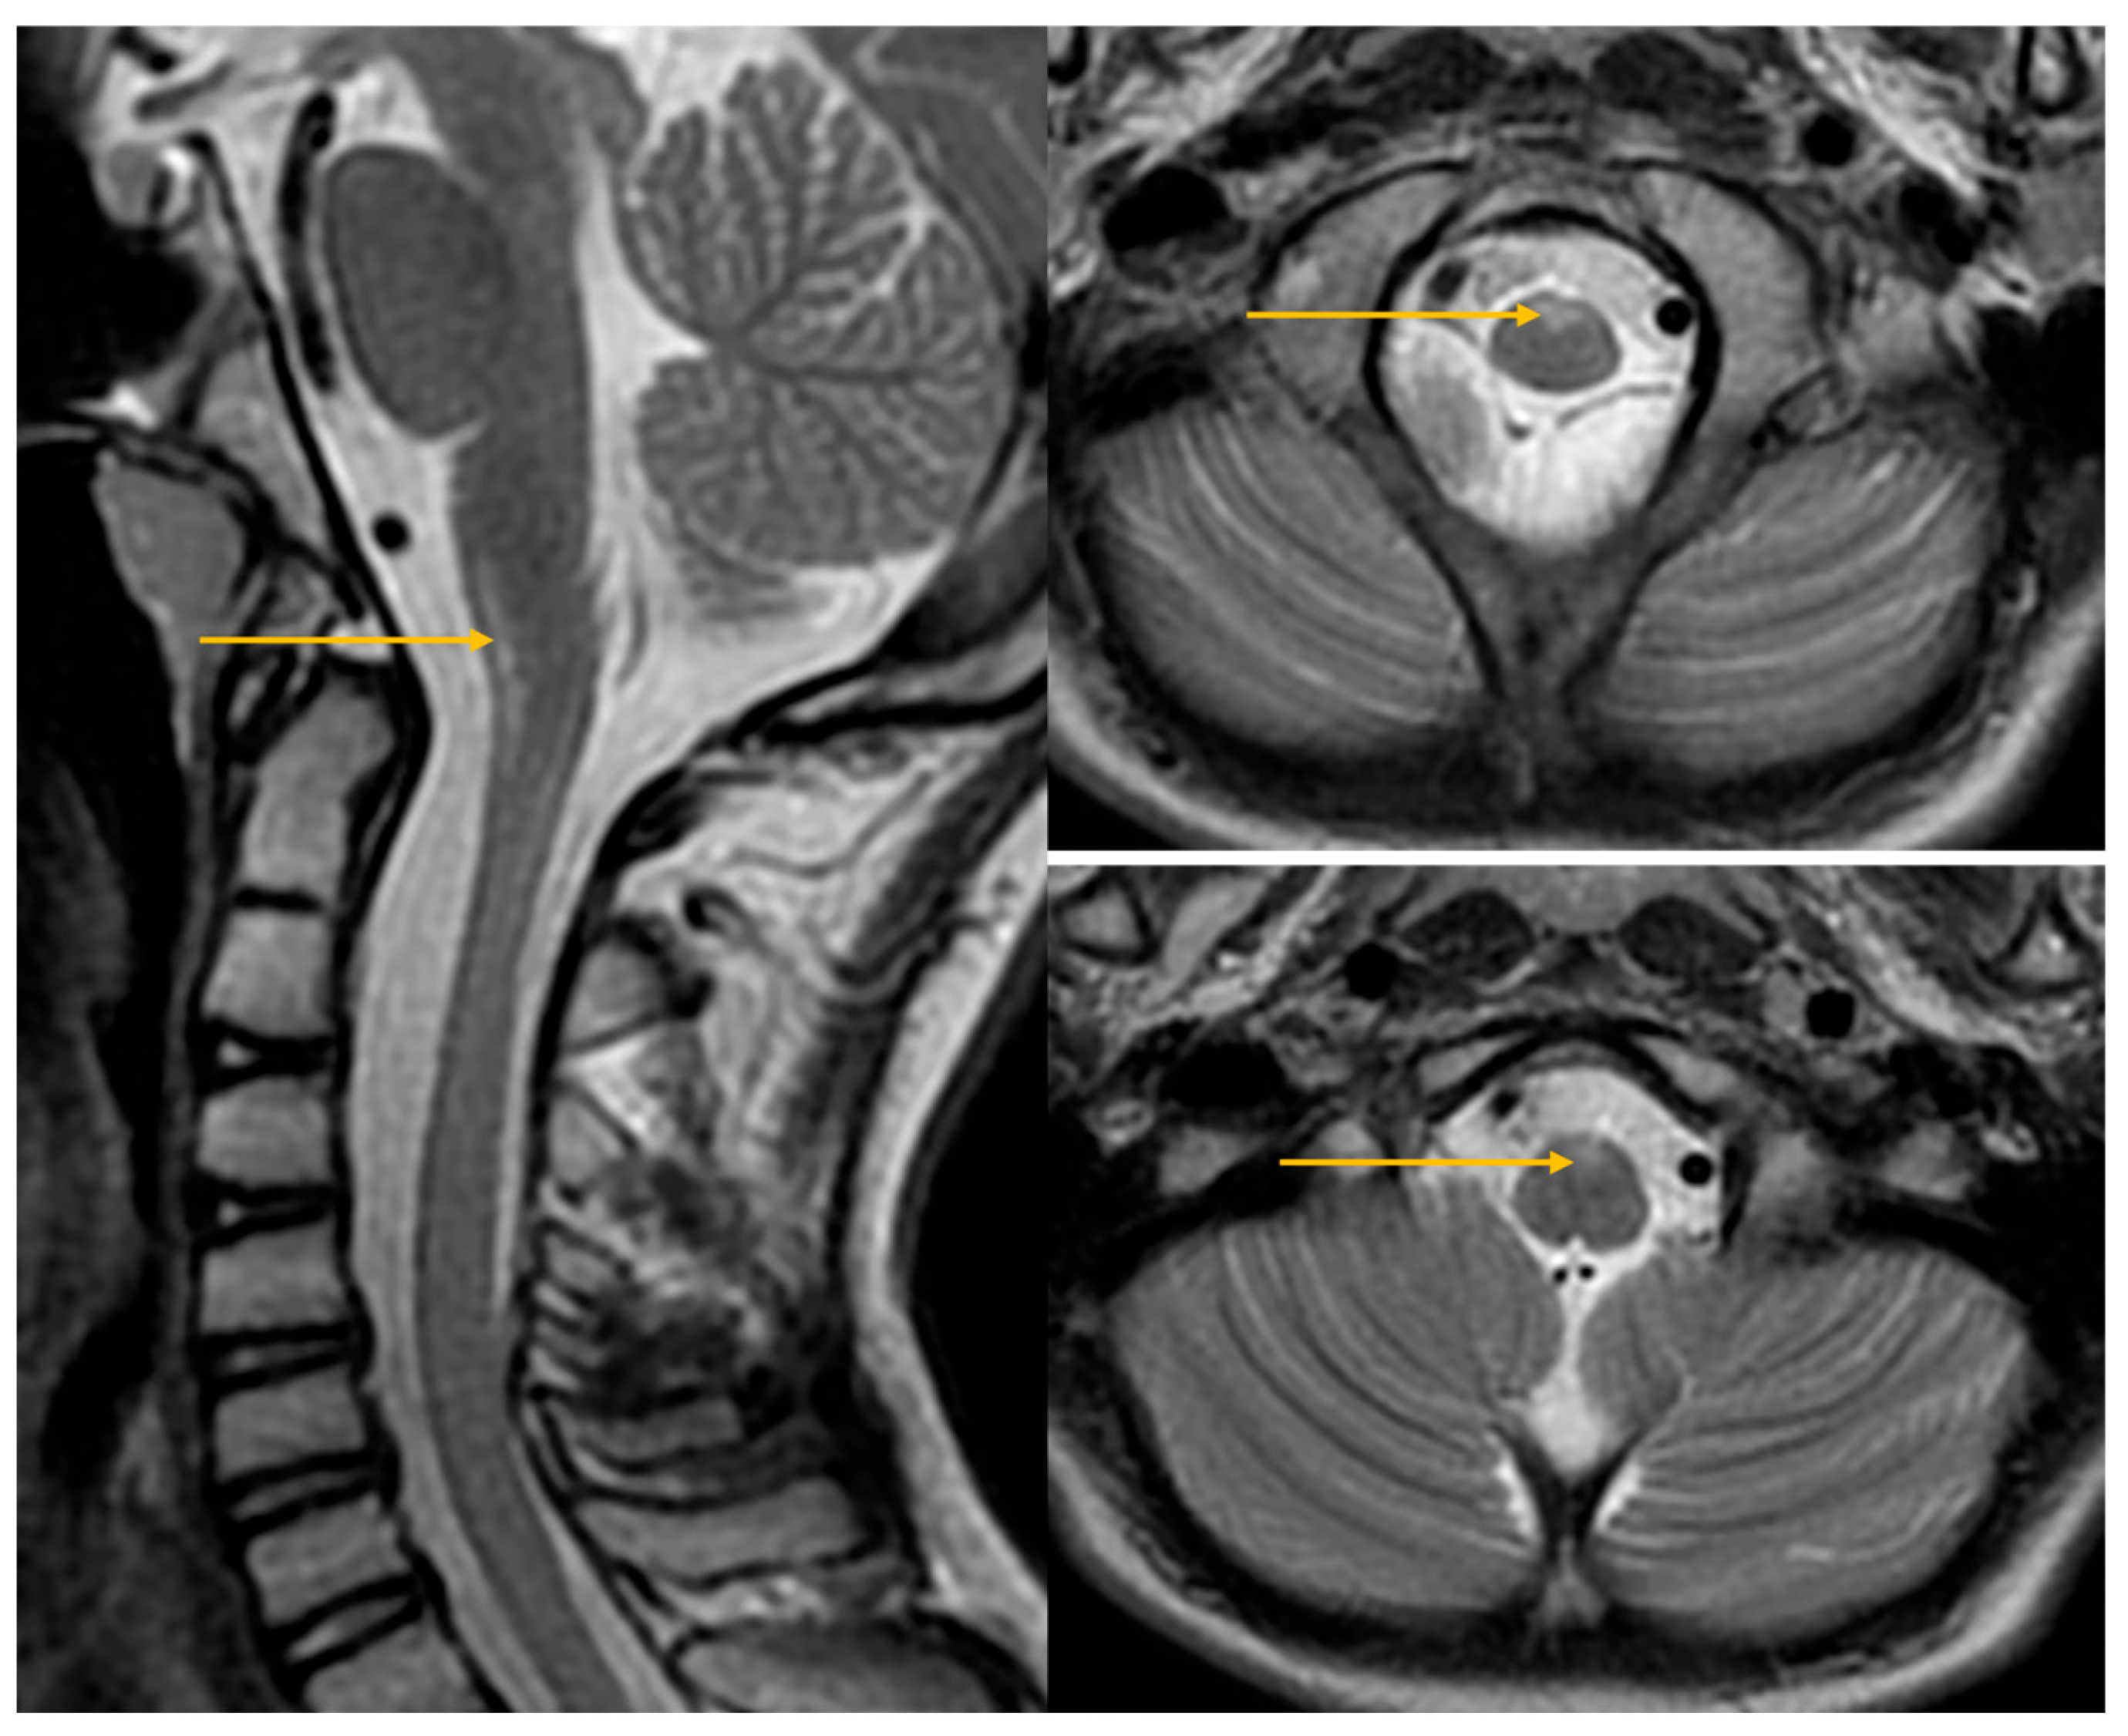

| Abnormal signal intensity of the anterior portion of the medulla oblongata | Yes | NA | Yes | Yes | Yes | Yes | Yes |

| Atrophy of the medulla | No | NA | No | Yes | Yes | Yes | Yes |

| Atrophy of the cervical spinal cord | Yes | NA | No | Yes | Yes | Yes | Yes |

- Neuroimaging characteristics